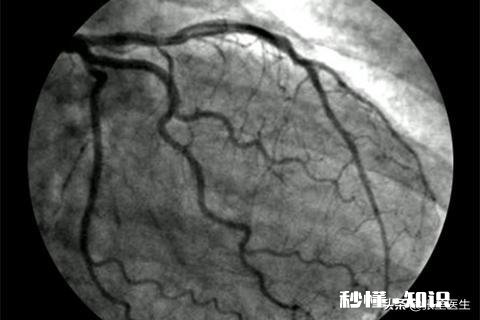

⑤导管及心血管造影检查:用于其它诊断手段难以确诊的心脏疾病 。目前冠状动脉造影是诊断冠状动脉粥样硬化性心脏病的“金标准”,可以明确冠状动脉有没有狭窄、狭窄的部位、程度、范围,并为治疗方法提供依据 , 同时可以进行左心室造影,对心功能进行评估 。

文章插图